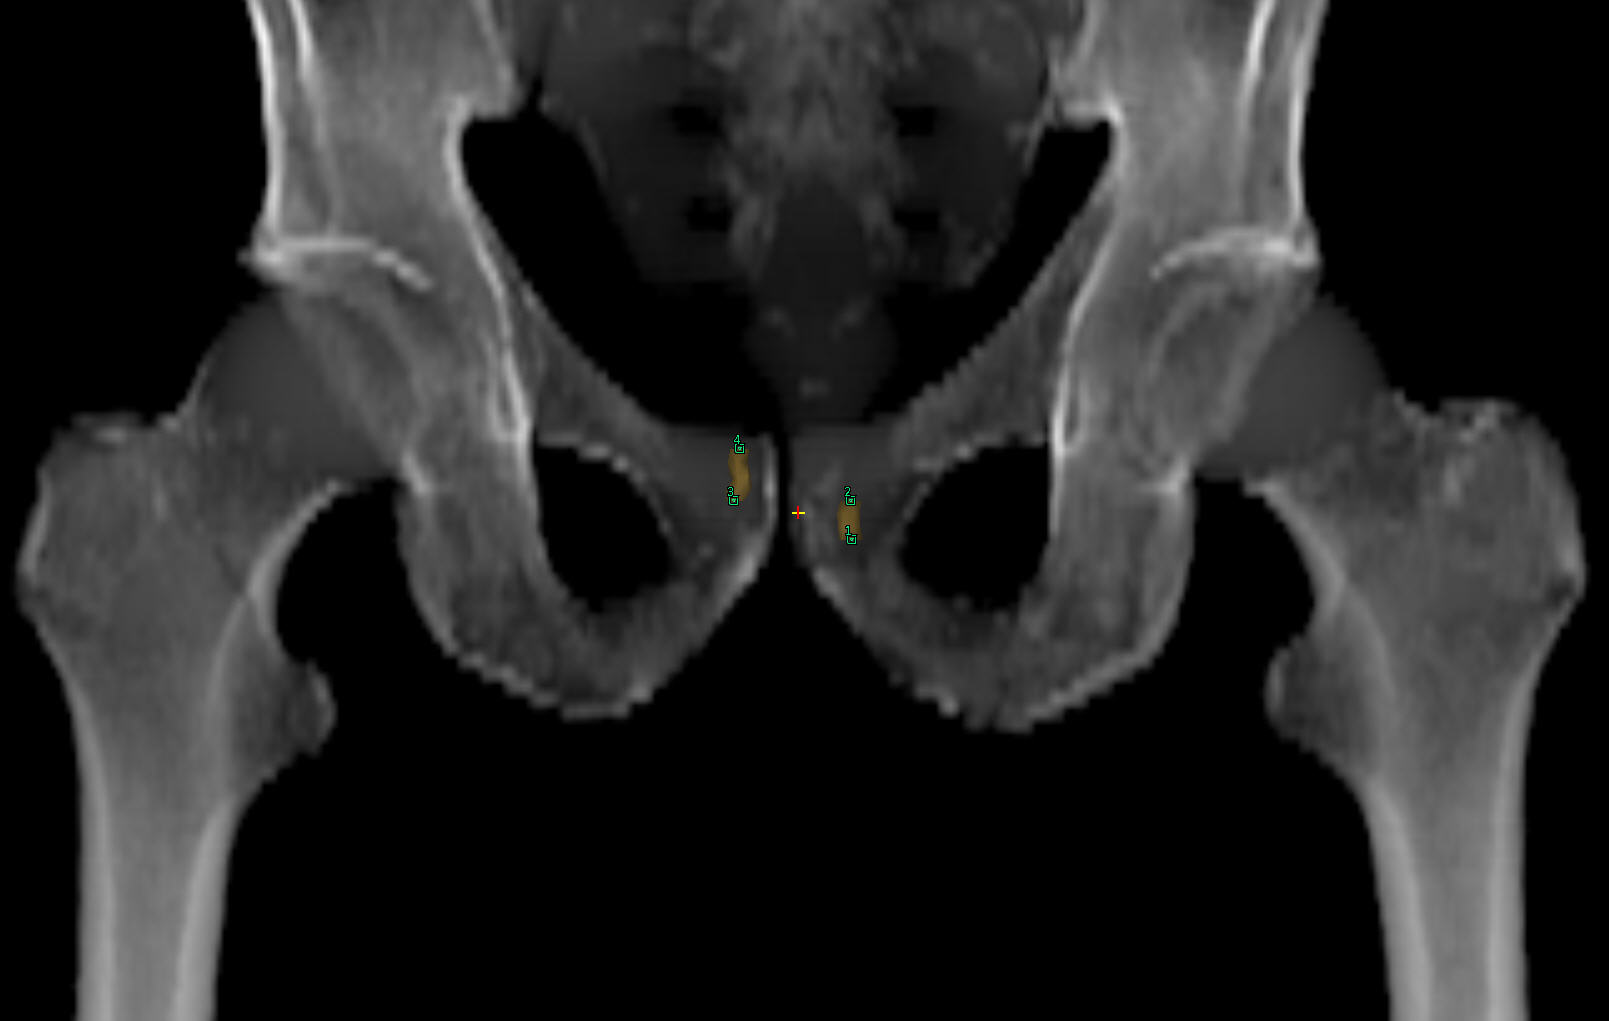

77-year-old male with prostate cancer cT3aN0M0, Gleason 8 and PSA 52 µg/L referred to androgen deprivation and radiation therapy with a prescribed dose of 50 Gy to the pelvic lymph node regions and 76 Gy to the prostate. Patient underwent MRI on Ingenia MR-RT 1.5T using FlexCoverage Anterior Coil in combination with the integrated Posterior Coil. Dose planning was performed on MRI imaging data.